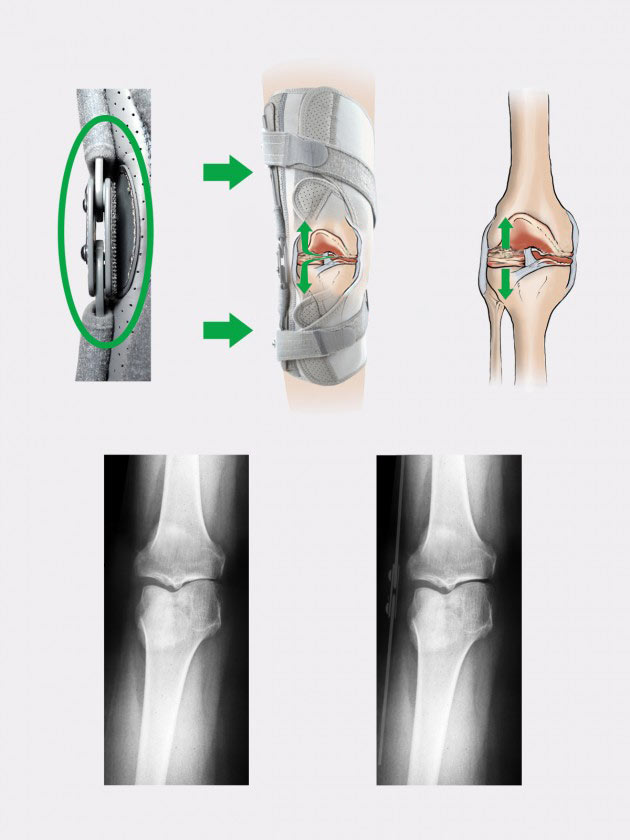

На концах шины есть две поворотные пряжки, через которые проходят динамические спиральные ремни, стабилизирующие коленный сустав и разделяющие поверхности сустава что уменьшает боль и предотвращает прогрес остеоартрита.

2-осевая шина 2RP

Шины 2RP - это двухосные ортопедические шины, которые при сгибании точно отражают движение коленного сустава во время ходьбы, так что их шарниры не меняют своего положения по отношению к оси коленного сустава. Шины 2RP представляют собой армированные двухосные полицентрические шины, снабженные шарнирно-сочлененным механизмом, основным элементом которого являются направляющие, движущиеся по параболическим путям. Этот тип шин в основном используется в коленных ортезах, где важны сильная боковая стабилизация коленного сустава и точное регулирование его подвижности. Плечи шин изготовлены из высококачественного алюминиевого сплава, с горячим нанесением прочного порошкового покрытия, что делает их очень легкими, а их поверхность устойчива к воздействию пота пациента и содержащейся в нем соли. Шарниры изготовлены из очень прочного и твердого кислотоупорного листового металла, в котором прорезана соответствующая система отверстий, сделаны соответствующие резьбы, они также защищены порошковой краской. Шины водостойкие и могут использоваться во влажной среде.

Шарниры имеют блокировку переразгибания сустава, блокировку сгибания: 0 , 10, 30, 40, 60, 75, 90 градусов, а также блокировку разгибания: 10, 20, 30, 40 градусов. Регулировка угла осуществляется с помощью специальных закаленных винтов с шестигранной головкой, которые ввинчиваются в резьбовые места, отмеченные конкретными значениями углов, которые мы хотим зафиксировать. В шине 2RP можно заблокировать не только углы сгиба коленного сустава и углы его разгибания, но и желаемый диапазон движения сустава. Каждый ортез, оснащенный шинами 2RP, поставляется с бесплатным шестигранным ключом для выполнения этих настроек. Такой метод регулировки часов в ортопедических шинах предотвращает вмешательство в их настройку посторонними лицами, не имеющими ключа. Внутренняя часть шарниров имеет овальную форму, что позволяет прикрепить мягкую анатомическую подушку, выполненную в 3D-технологии, которая отделяет их от колена. Все подвижные элементы шин перемещаются на заклепках из оцинкованной стали, а для предотвращения их заклинивания в этих местах использовались специальные тефлоновые ползуны. Такая конструкция обеспечивает их безотказную работу, также они не нуждаются в смазке и обслуживании.